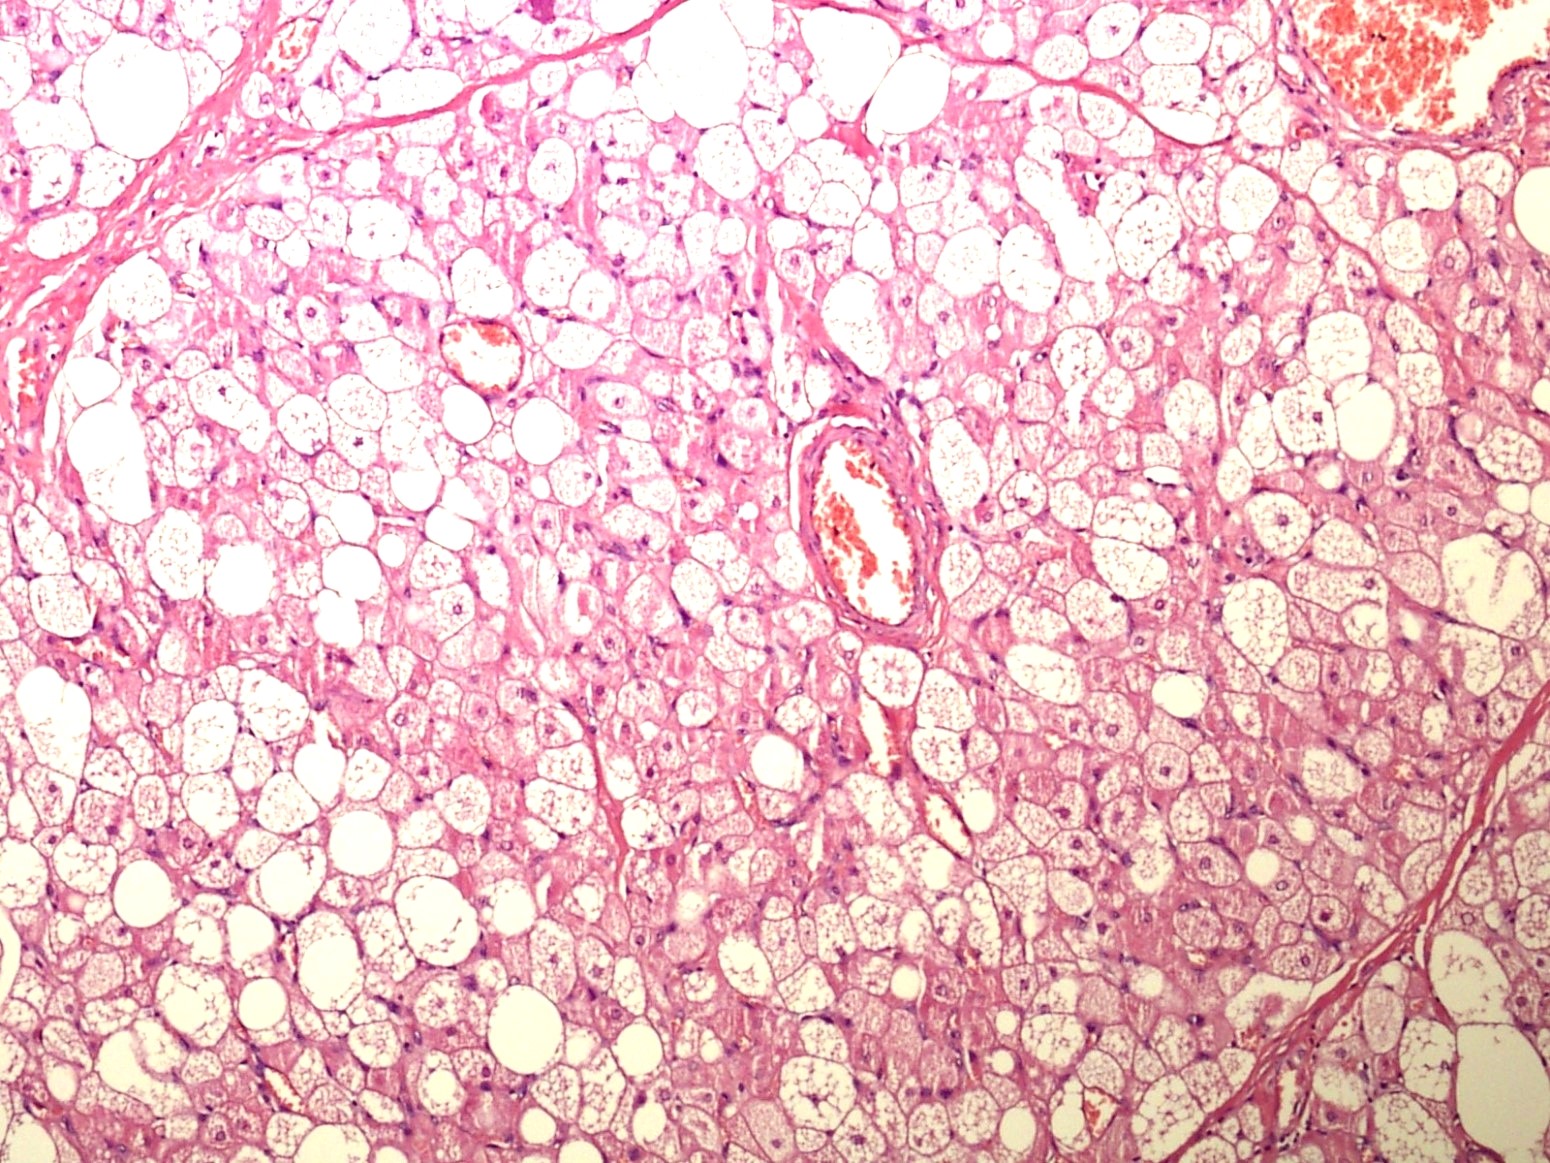

Microscopic (histologic) description

- Neoplastic lesion composed of polygonal brown fat cells with stromal cells in the background (Case Rep Oncol 2017;10:438)

- Large number of pale and eosinophilic brown fat cells with multivacuolated, eosinophilic granular cytoplasm and small central nucleus (about 70%) admixed with variable amount of univacuolated white cells (Case Rep Oncol 2017;10:438, Am J Case Rep 2020;21:e921447, J Comput Assist Tomogr 2019;43:793, J Pathol Transl Med 2017;51:499, Am J Surg Pathol 2018;42:951, Virchows Arch 2021;478:527)

- Multivacuolations resemble lipoblasts

- Morphological variations or subtypes: typical, myxoid (9%), lipoma-like (7%), spindle cell (2%), thick bundles of collagen fibers, presence of mast cells and exclusively containing brown fat cells (Case Rep Oncol 2017;10:438, Am J Case Rep 2020;21:e921447, Virchows Arch 2021;478:527)

- Cytological atypia, necrosis and mitosis is unusual (J Pathol Transl Med 2017;51:499, Am J Surg Pathol 2018;42:951, BMC Surg 2021;21:30)

Microscopic (histologic) images